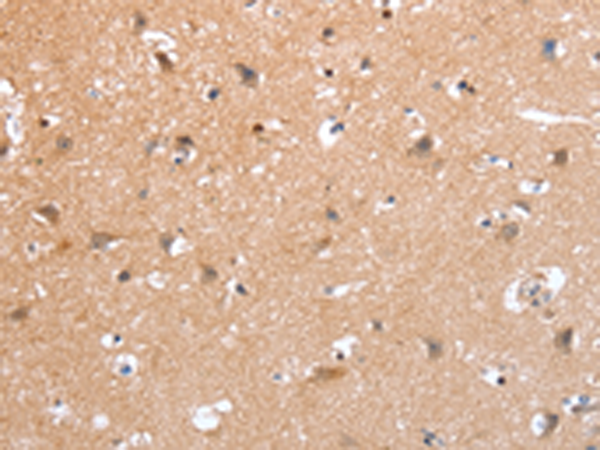

分类: 科研抗体货号: P11133别名: MTK1; MEKK4; MAPKKK4; PRO0412应用: IHC反应种属: Human